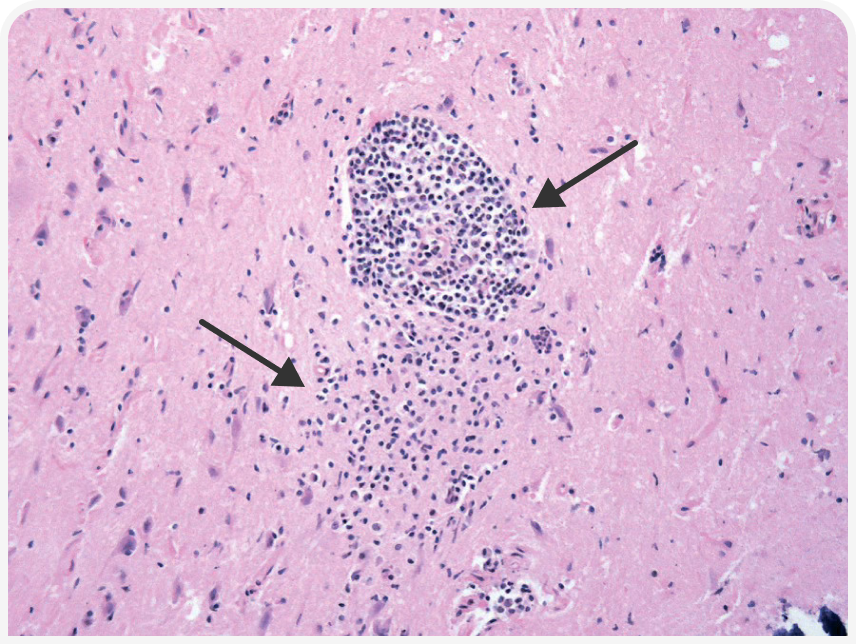

Внутриклеточный рост микроорганизма вызывает прямое цитопатическое действие с воспалением и некрозом клеток хозяина, проявляющееся более специфическими симптомами в зависимости от локализации тахизоитов в организме (Рисунки 4–6); возможны поражение глаз, неврологические симптомы, пневмония, желтуха (4).

Прогноз для кошек с клиническими проявлениями токсоплазмоза зависит от ряда факторов, в том числе от пораженных систем/органов (Рисунки 7 и 8) и времени, прошедшего от момента заражения до начала лечения. Как правило, если в течение 2–3 дней после начала терапии клинические проявления улучшаются, прогноз благоприятный, но прогноз при поражении легких или печени неблагоприятный (4).